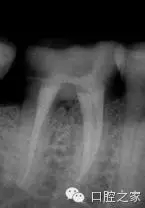

若干雜志均報(bào)道了近中牙根內(nèi)第三根管的存在。本篇系統(tǒng)性文獻(xiàn)回顧報(bào)道的是2.6%的第三根管發(fā)生率(圖2和3)。為了進(jìn)一步定位第三根管,需要對開髓洞形進(jìn)行改良。簡單地講,一旦定位了主根管,并對其進(jìn)行根管預(yù)備后,使用小球鉆或超聲工作尖去除根管口間的牙本質(zhì)橋,為近中根的近中壁與髓腔形成的角提供了直視的視野,將兩個(gè)主根管間發(fā)育溝直接暴露出來。然后使用根管口探針探查根管,小號(hào)的根管銼順利的通暢根管。除此之外,手術(shù)顯微鏡的運(yùn)用進(jìn)一步提高了發(fā)現(xiàn)和治療副根管的可能性。還有一點(diǎn)必須要考慮的是近中根的遠(yuǎn)中凹度,為了避免出現(xiàn)帶狀穿孔,第三個(gè)近中根管的預(yù)備過程要使用小號(hào)的根管銼謹(jǐn)慎小心的預(yù)備。中間近中根中根管完全獨(dú)立的患牙占整個(gè)病例中的25%。